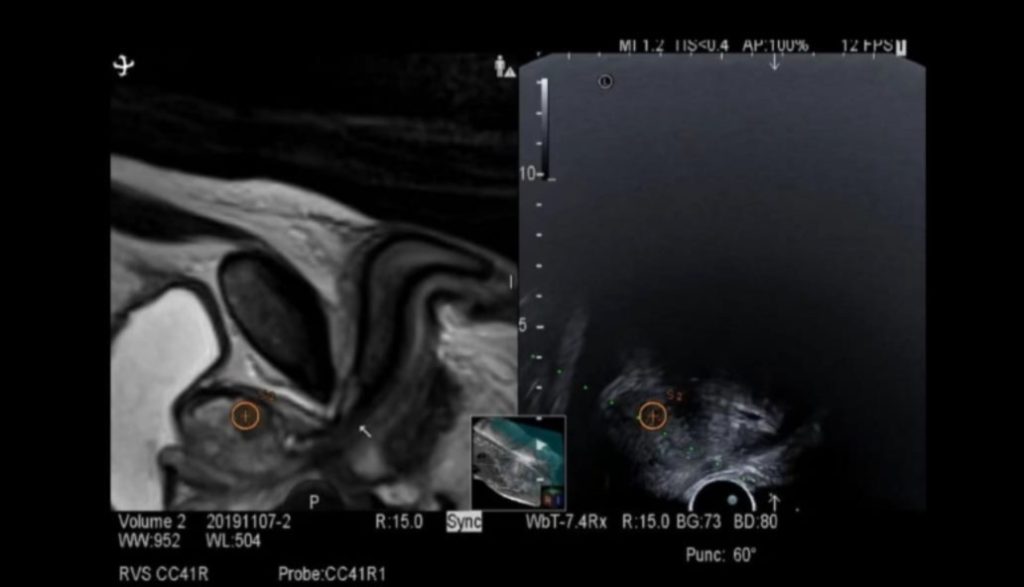

Biopsia RMN-fusion combină imagistica prin rezonanță magnetică multiparametrică (IRM/mp) cu ghidarea ecografică transrectală, permițând medicului să identifice și să preleveze țesut exact din zonele suspecte identificate ale prostatei. Astfel, precizia diagnosticului crește semnificativ comparativ cu biopsiile clasice realizate „în orb”.

Principiul procedurii se bazează pe suprapunerea imaginilor obținute anterior prin RMN peste imaginile ecografice în timp real. Software-ul dedicat fuzionează cele două seturi de date, generând o hartă tridimensională detaliată a prostatei. Această abordare permite prelevarea țintită a probelor din leziunile cu risc crescut, identificate anterior prin RMN ca fiind suspecte conform scorului PIRADS.